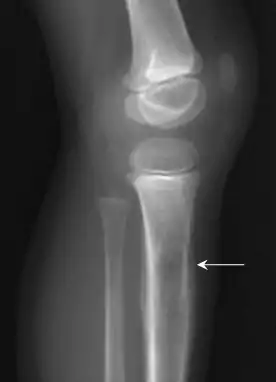

![]() Rayos X de un niño con sarcoma de Ewing en la tibia | ||

En radiografías convencionales, la manifestación ósea más común es una lesión litica extendida con reacción en el periostio. La descripción clásica del tipo de reacción periostica en forma laminada o en «piel de cebolla» es a menudo asociado con esta lesión. Las radiografías simples proporcionan valiosa información en la evaluación inicial o exploración. Las amplias zonas de transición es la característica más útil de las proyecciones simples para diferenciar los tumores benignos de los agresivos o lesiones líticas malignas.[13]